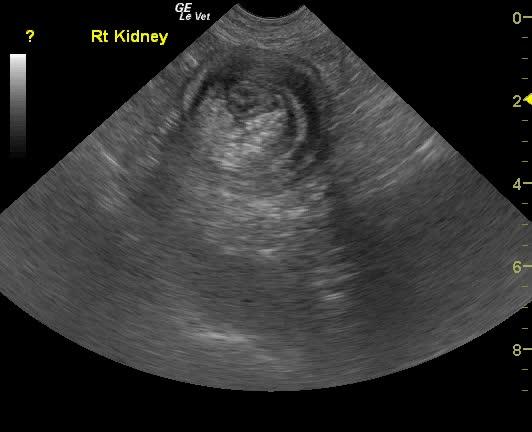

A 10 year-old MN Shepherd mixed dog presented with a 2-3 month history of intermittent vomiting and a more recent anorexia. Abnormalities on physical examination were dehydration and a 3 cm firm left anal sac mass. The only significant finding on CBC and serum biochemistry was hypoalbuminemia. Survey radiographs showed no evidence of pulmonary metastases but revealed excessive pyloric gas pattern with a volume contracted heart.